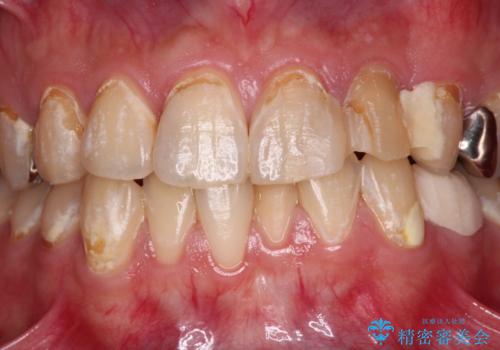

- むし歯の影響で、前歯を見せることが恥ずかしいとのことで来院された患者様です。

全顎的にむし歯が多く、治療が必要な歯はたくさんありましたが、まずは非常に目立つ前歯から処置を行うこととしました。

むし歯は歯肉内にまで進行していると外科処置が必要となりますが、ギリギリの位置でとどまっていたため、速やかにオールセラミッククラウンにて補綴治療することとしました。